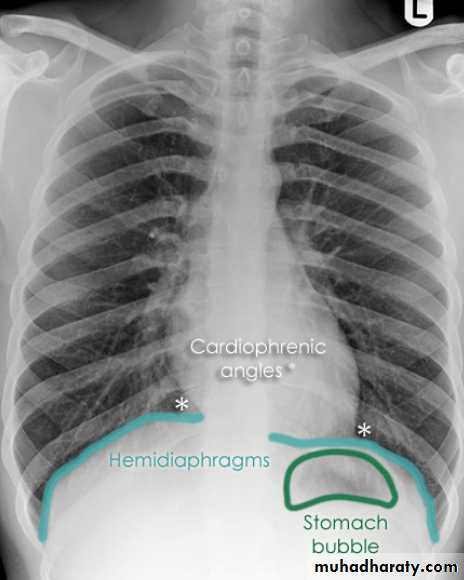

Look carefully on both diaphragmatic cruse costo & cardio phrenic angles

Don't forget to use rib in asses lung Zones

10.normal chest anatomy

11.Radiological lung zone